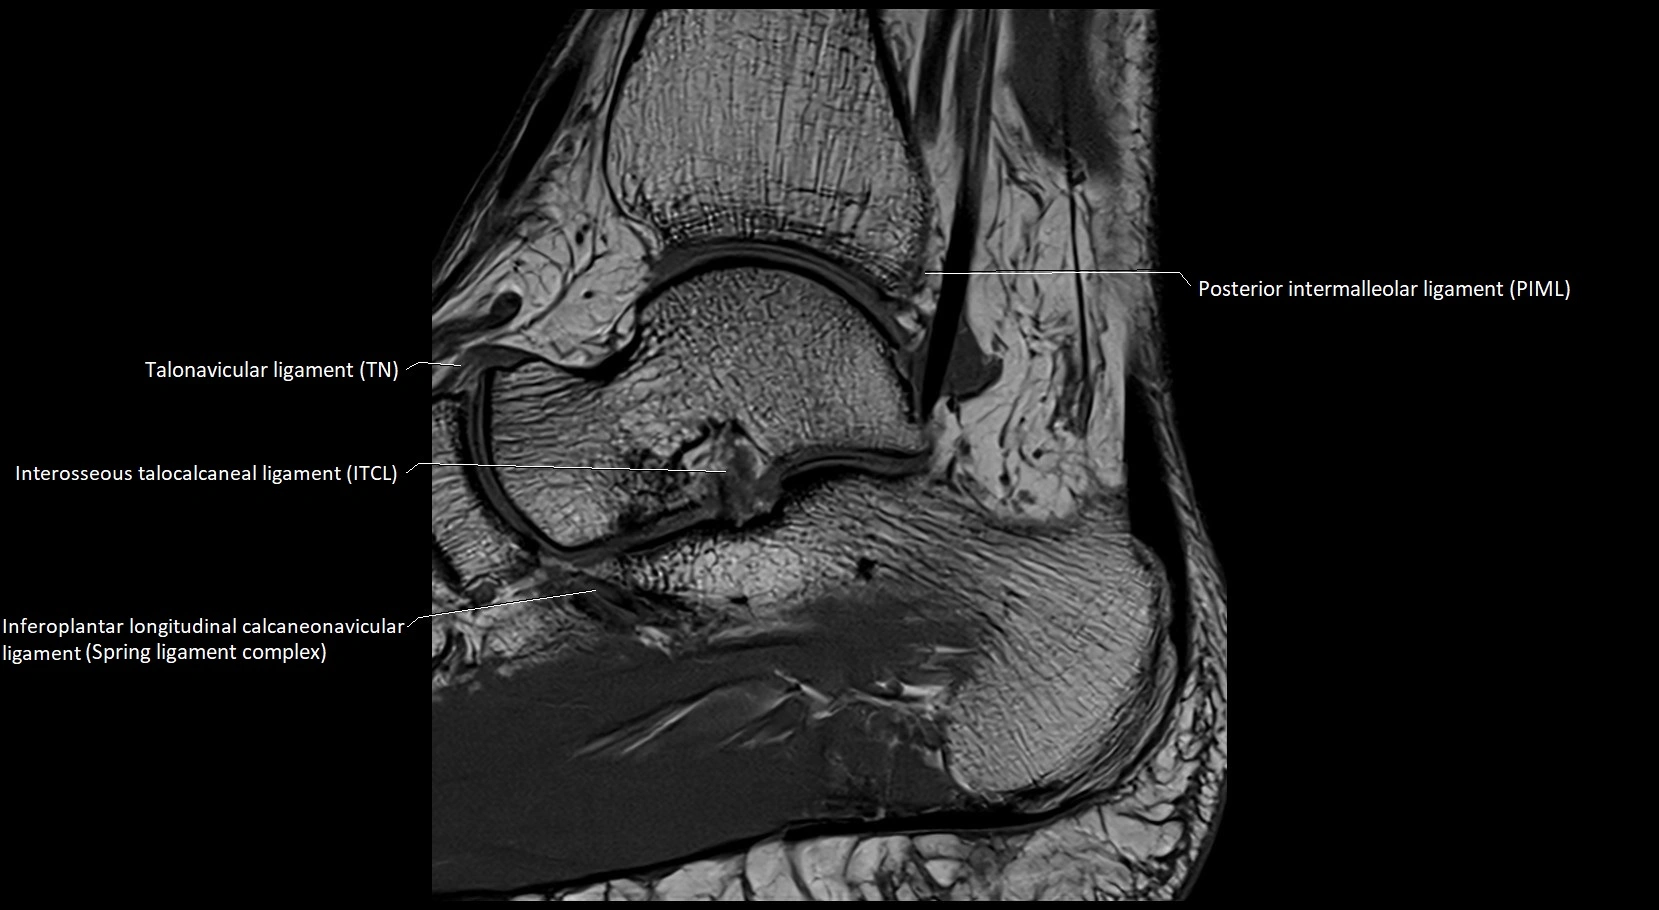

MRI image

image